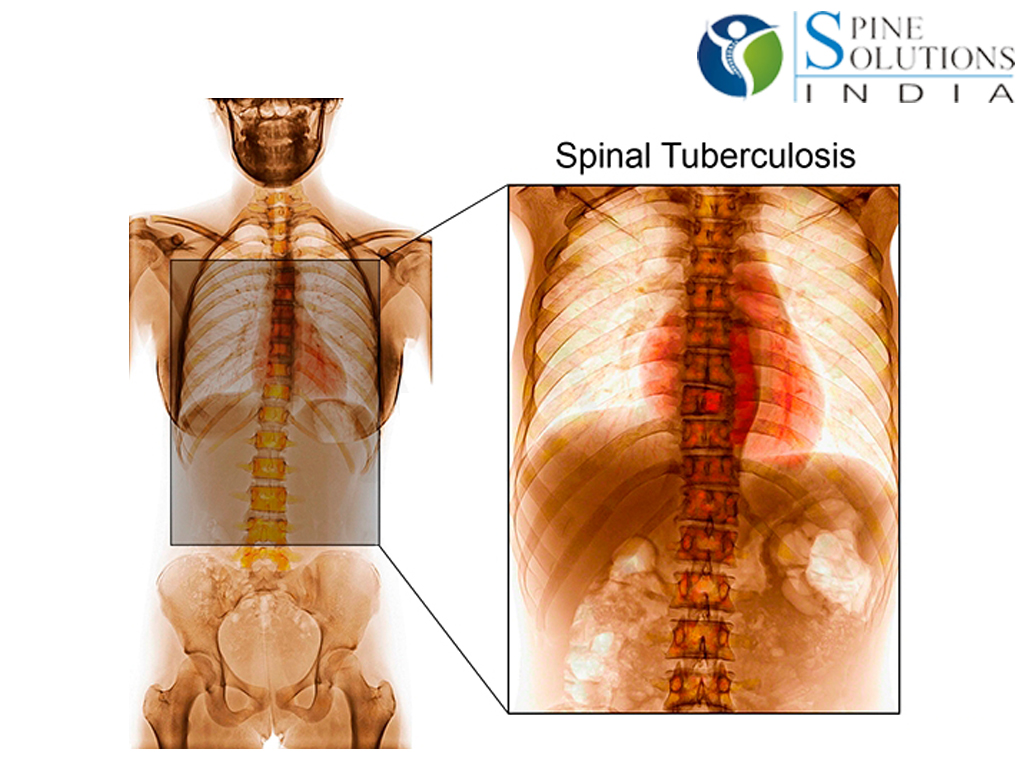

Симптомы и признаки туберкулеза: как распознать заболевание

Раздел: Визуальные уроки